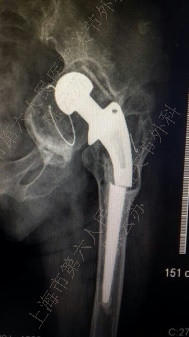

采用个性化人工垫块重建髋臼周围骨缺损的两例患者,手术中及术后影像学检查均证实个体化人工垫块与髋臼面骨缺损匹配完全,固定牢靠,髋臼假体安放及螺钉置入位置及角度理想,无血管神经损伤等并发症出现。目前两例患者分别随访1年及六月,X光片复查臼杯及垫块均固定在位,周围骨组织长入良好。

图1

患者。女性,65岁,左全髋关节置换术后18年,疼痛12年,加剧2年。图1:术前,图2:CT模拟设计,图3:3D打印模块,图4:术中缺损填充,图5:术后片,图6:术后1年随访片